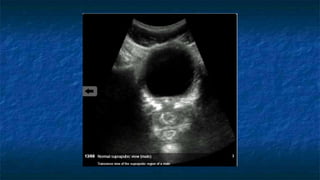

1) Subxiphoid exam

 Probe placed

 Transversally

 Midline plane

 Just below subxiphoid region

 Probe facing towards patient’s right

FAST: Subxiphoid exam

 Normal Anatomy

 Liver at very top of screen

 Epicardial fat vs. effusion

 Thin layer anterior to

RV

 Not present posterior

to LV

Normal Subxiphoid exam